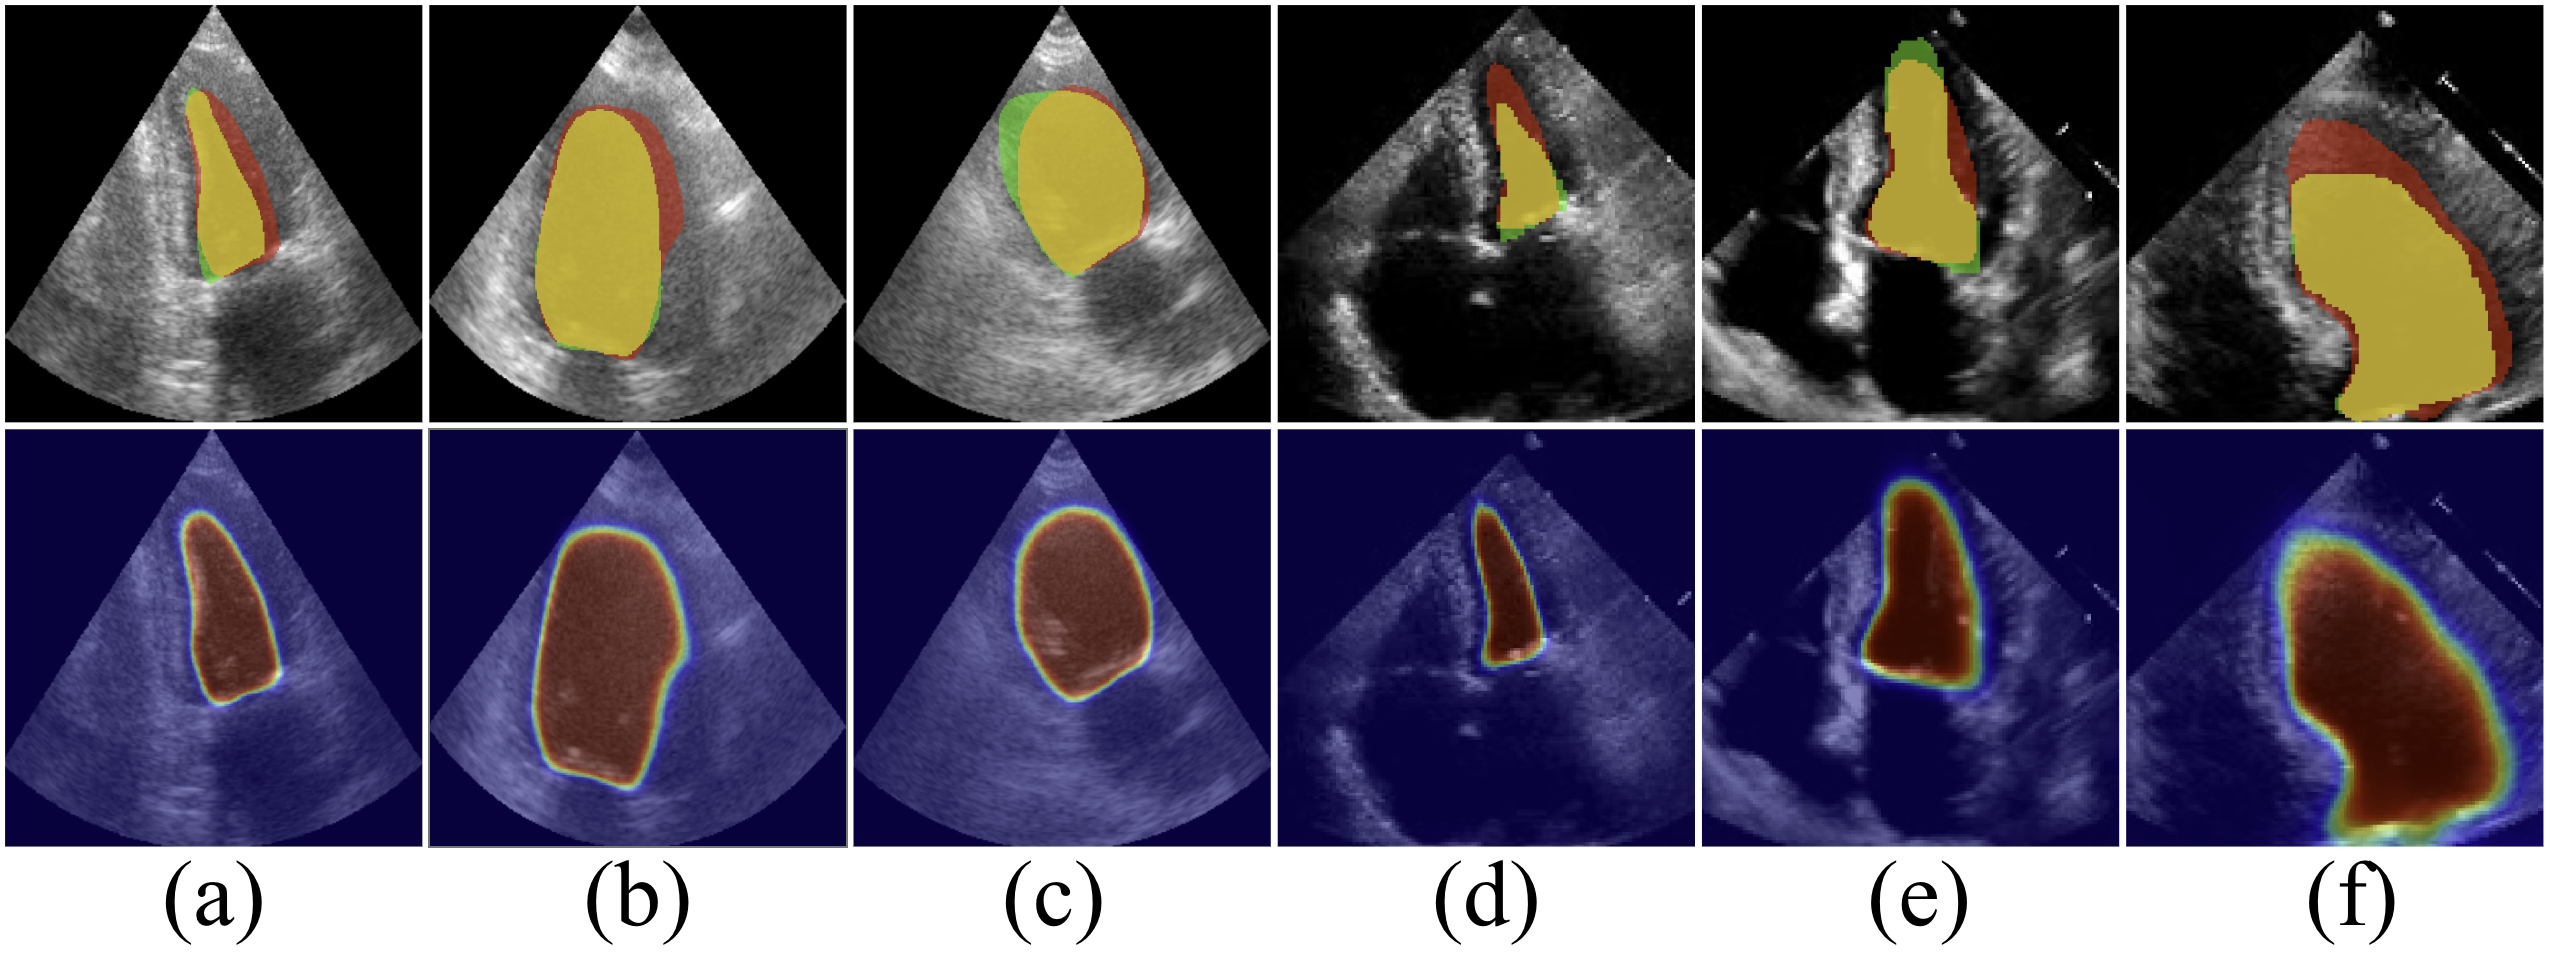

Refer to caption

Figure 8: Visualization of segmentation results using different ablation strategies of GDKVM on CAMUS. The heatmap colors indicate prediction confidence, with warmer colors denoting higher confidence.

4.3 Ablation Studies

To evaluate each component of GDKVM, we performed ablation studies on CAMUS, as shown in Figs. 8 and 3.

Effectiveness of Key-Pixel Feature Fusion.

KPFF mechanism is critical for handling the significant scale variations and spatial transformations inherent in echocardiography videos. Disabling this mechanism and relying on a single key feature extraction approach causes a marked degradation in segmentation performance (Tab. 3). The model becomes particularly vulnerable to image noise and distortion, leading to less accurate boundary delineation, as visually evidenced in Fig. 8. These results establish that the proposed feature fusion is essential for achieving robust and precise segmentation in such dynamic clinical data.